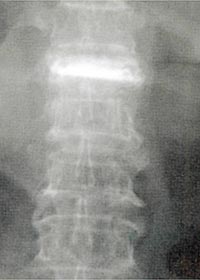

医生在折裂的部分注入骨胶,治疗骨折。

采用先进的放射科技,医生不需进行开刀也能看到体内的情况,他们只要把一支粗针在不伤害到脊髓和器官的情况下、推入折裂的部分,然后注入一些骨胶即可。